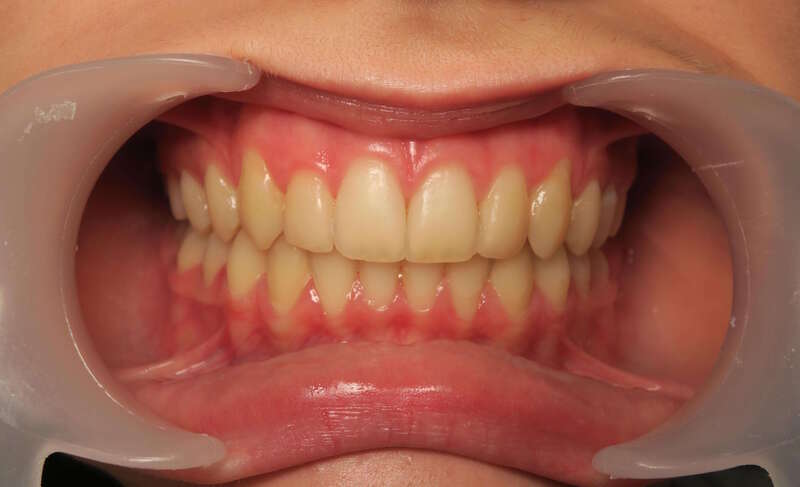

Cas n°1 traité par aligneurs - adolescent

Ce cas d’une adolescente illustre la correction d'une Classe II avec supraclusion par aligneurs. La stratégie thérapeutique a reposé sur une distalisation séquentielle de l'arcade supérieure. Ce mouvement précis a permis de reculer les dents maxillaires étape par étape pour annuler le surplomb (overjet) sans extractions.

• Correction fonctionnelle : Retour à un engrènement de Classe I stable et correction du recouvrement vertical.

• Esthétique restaurée : Harmonisation globale du sourire et du profil.

Le résultat final montre une occlusion saine et un sourire parfaitement aligné, garantissant une santé dentaire et articulaire optimale pour l'avenir.

Avant

Après